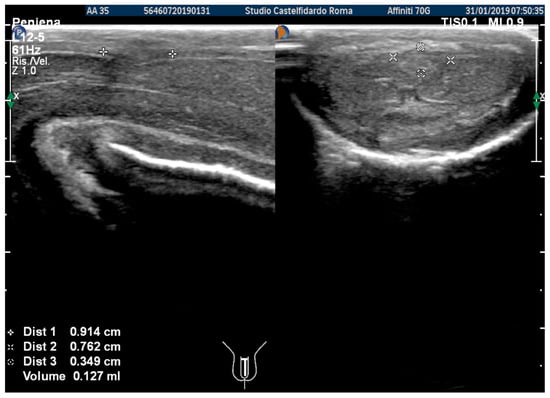

At the end of the second cycle of treatment, the patient underwent follow-up with a physical exam and a penile Doppler ultrasound. At follow-up, the IIEF score was 27. We then observed a dorsal penile curvature with an angle reduced to 15 degrees. The penile ultrasound showed the following plaque dimensions: 9.14 × 7.62 × 1.27 mm (127 mm3 = volume) (Figure 11).

Figure 3. Ultrasonography of the penis after the 2nd therapy cycle (longitudinal and axial views).

Figure 11. Ultrasonography of the penis after the 2nd therapy cycle (longitudinal and axial views).